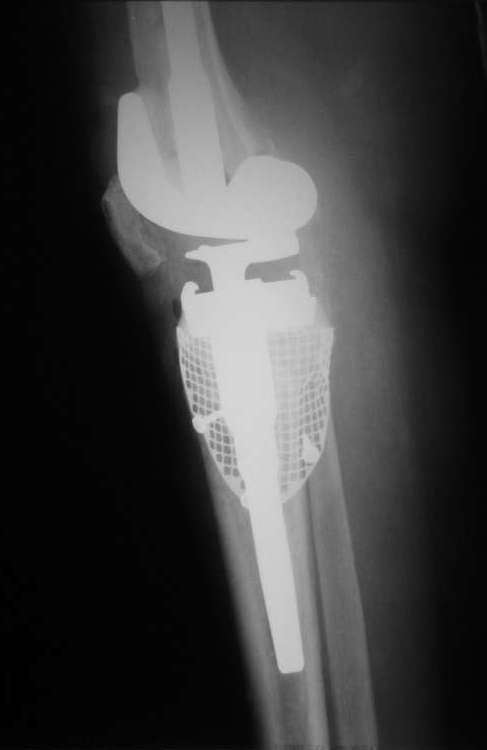

Рассверлили канал большеберцовой кости. В канал поставили стержень. По нему, на наружный кортикал посадили шаблон тибиального компонента (см. фото). Определили размер дефекта внутреннего мыщелка, который надо закрыть сеткой.

На внутренний мышелок установили сетку из нержавеющей стали Ex-Change Stryker (предназначенную для укрепления верхнего края вертлужной впадины) и фиксировали её 4 винтами. Подрезали сетку сверху по шаблону тибиального компонента. После этого рассверлили канал б/б и бедренной костей под протез. Используя систему пульс-лаважа Stryker SurgiLav c насадкой - щеткой для промывания каналов промыли бедренную и большеберцовую кости. Последнее сверло, которым рассверливали проксимальную часть канала б/б кости, оставили на месте. Аллотрансплантат перемололи на костной мельнице, перемешали с 3 гр. ванкомицина и достаточно плотно заполнили им дефект внутреннего мыщелка, утрамбовывая импактором костную стружку в единую массу.

Так как наружный кортикал был на 1.3 см. ниже головки малоберцовой кости, пришлось использовать вставку под большеберцовый компонент 1 см. На цемент c ванкомицином поставили тибиальный компонент с ножкой 11/80 мм.

Бедро по шаблону резецировали (лучше сказать «причесали»). Системой пульс-лаваж с щеткой для отмывания костной поверхности основательно все отмыли и поставили на цемент бедренный компонент c ножкой 11/155 мм.

1) Парез малоберцового нерва. - Через 2 дня после операции чувствительность восстановилась, движений пока нет. Связываем с существенным удлинением ноги при установке протеза.

2) У нас не было пистолета для ретроградного заполнения канала большеберцовой кости. После импакции костного трансплантата без пистолета зацементировать ножку большеберцового компонента, не повреждая при этом утрамбованный трансплантат, оказалось не так просто.

3) На бедре сохранились только внешние стенки мыщелков. Поэтому размер бедренного компонента выбирали по ним, а не по переднезадним размерам бедра. В результате бедренный компонент повис на 2 мм над передним кортикалом. Пытались сместить бедренный компонент назад при помощи 4 мм офсетного адаптера, но конструкция протеза не позволила этого сделать. Основание модульной ножки бедренного компонента уперлось в заднюю стенку бедренной кости.

4) Когда стали зашивать рану, пришлось мобилизовать мягкие ткани для закрытия дистального конца раны.

Сейчас ждем, как поведет себя аллотрансплантат и малоберцовый нерв. Слава богу, положительная динамика есть… Рана спокойна.

Учитывая массивную пластику, пациента будет ходить без нагрузки на ногу до 6 недель, а там посмотрим по рентгенограммам. Большой опасности от дозированной нагрузки не вижу, так как ножка тибиального компонента нашла опору в здоровой плотной кости.

Не давать нагрузку тоже нельзя – трансплантат не сформирует нормальную кость.

Буду признателен за советы со стороны более опытных коллег по дальнейшему ведению пациентки.

Абсолютно справедливо Михал Беренштейн заметил, что линия сутавной щели ушла вверх примерно на 1 см. По хорошему, надо было поставить под tibia блок в 0.5 см и 0.5 - 1 см. блоки под бедро. Рассотяние от надмыщелков до суставной шели сейчас около 2 см.

Виноват - пошли на операцию с минимумом возможных вариантов имплантов + аллотнаспланта было маловато. Сейчас сгибание градусов 60, но после установки имплантата сгибали до 120, надколенник во вкладыш не упирался.